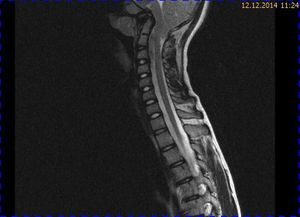

Abb. 1.3 Sagittales MRT (T2 TIRM): kein Hinweis auf mikrotrabekuläre Frakturen, regelrecht hydrierte Bandscheiben; die Kleinhirntonsillen lassen sich schlechter abgrenzen

Das Fallbeispiel 1 zeigt im Verlauf eine Komplikation bei einer Arnold-Chiari-Malformation Typ 1 bei einem zum Zeitpunkt der Erstdiagnose 12-jährigen Jungen. Dieser hatte im Sportunterricht einen schweren Medizinball geköpft und ein Stauchungs-trauma der Halswirbelsäule erlitten. Nach anfänglich symptomatischer frustraner Therapie wurde er vom behandelnden Orthopäden zur MRT der HWS überwiesen. Es wurde eine Streckfehlhaltung und flachbogig rechtskonvexe Skoliose diagnostiziert, klinisch bestand ein Torticollis. Eine knöcherne oder ligamentäre Verletzung wie auch eine Schädigung des Rückenmarks bzw. eine intraspinale Bandscheibendislokation konnten bildmorphologisch ausgeschlossen werden.

Trotz weiterer Schmerz- und Physiotherapie konnte keine Beschwerdereduktion erreicht werden. 2 Monate später erfolgte eine MRT des Kopfes zum Ausschluss einer posttraumatischen Veränderung.

Bei dieser Untersuchung wurde übersehen, dass die Kleinhirntonsillen in das Foramen magnum disloziert waren und eine Arnold-Chiari-Malformation mit Erweiterung des 4. Ventrikels und des Aquäduktes inklusive Kleinhirntonsillentiefstand vorlag. Bei zwischenzeitlich auswärtig erfolgtem CT der HWS wurde eine Anlagestörung im kraniozervikalen Übergang beschrieben. Eine Kontrolluntersuchung des Kopfes weitere 4 Monate später dokumentierte neben einem medullären Ödem einen progredienten Tonsillentiefstand, der zur neurochirurgischen Behandlung mit operativer Erweiterung des Foramen magnum führte.